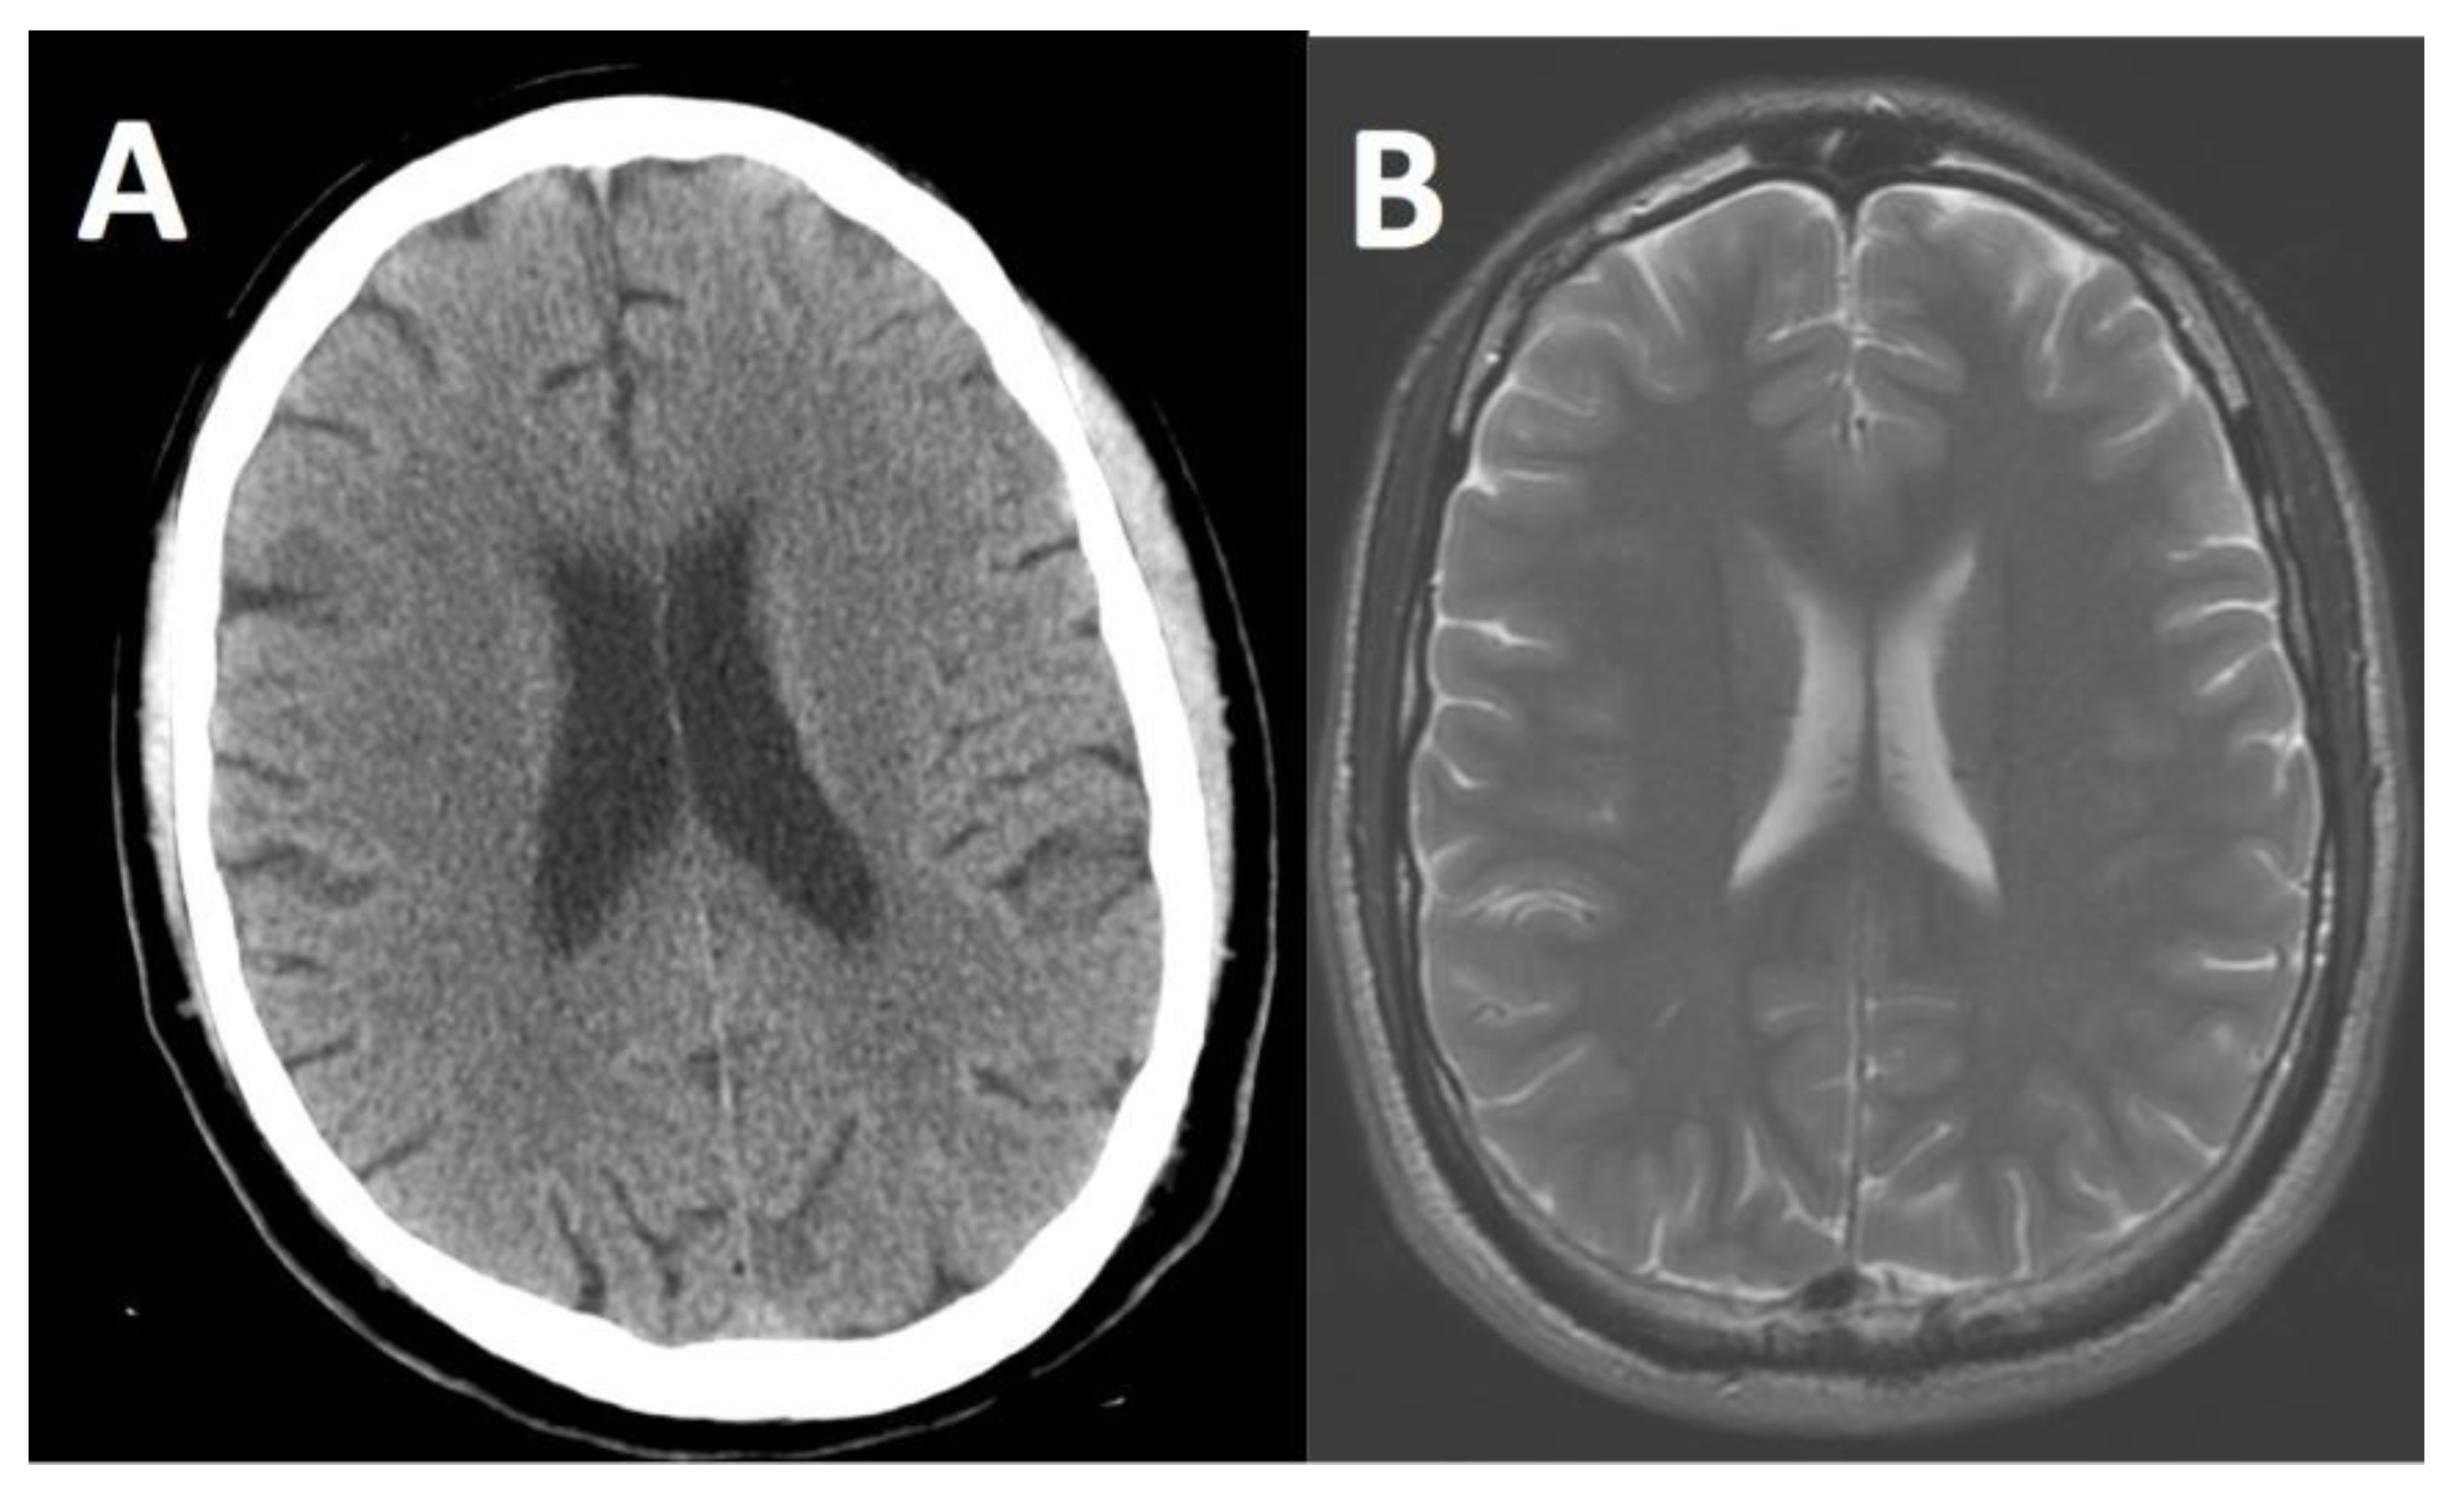

Figure 1.

Images of a normal brain in the axial plane. The head computed tomography (CT) image (A) shows the dense skull shown as white, the brain as a mid-gray shade and the cerebrospinal fluid as dark gray. The T2-weighted magnetic resonance imaging (MRI) image (B) shows the skull as black, the brain as a mid-gray shade with excellent gray matter and white matter differentiation and the cerebrospinal fluid as white.

Modern MRI scans require considerably more acquisition time than CT scans. For example, a brain MRI typically takes approximately 1 h. However, MRI does have superior contrast resolution of certain soft tissues, such as the gray matter and white matter in the brain as shown in Figure 1, and can enable diagnoses that are not possible with CT.